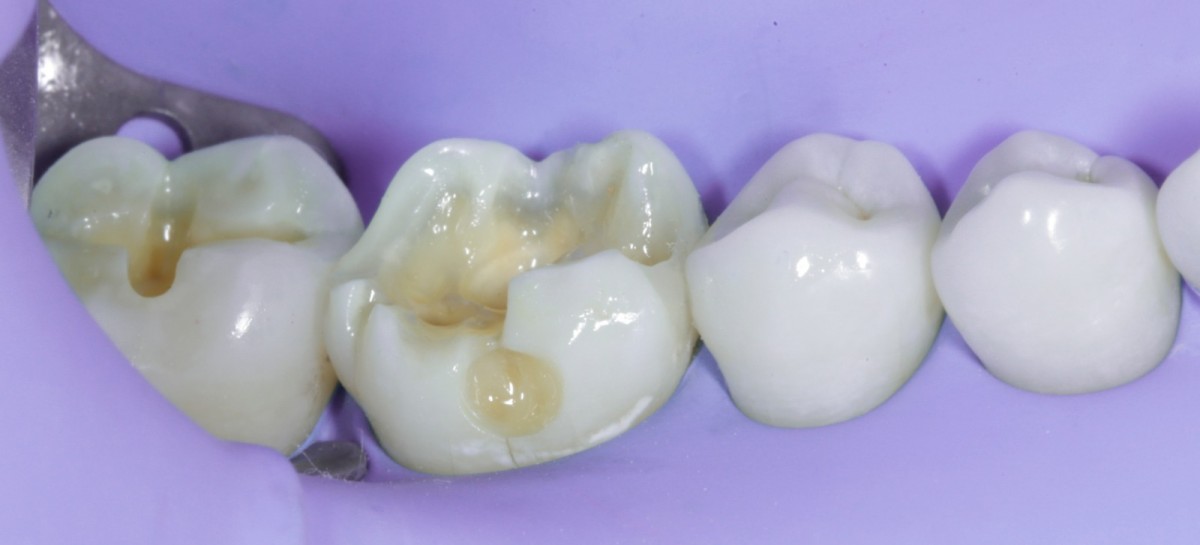

During the visit, consisting of the physical examination and instrumental examinations such as radiographs bitewings, thermal tests and compression tests (to exclude the presence of typical symptoms of a crack) at the level of the fourth quadrant, she has: amalgam restoration on dental element 4.6 associated with primary mesial caries and primary occlusal caries on 4.7.

The quadrant is rehabilitated through direct composite procedures.